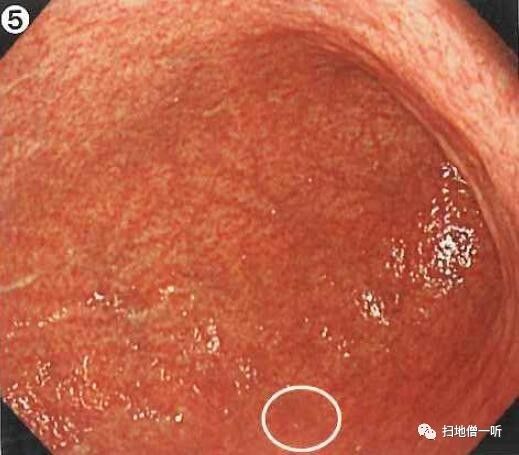

A:病变胃癌在图2。HP除菌后胃癌。

背景粘膜呈C-2型萎缩表现。萎缩领域容易出现分化型癌。胃窦部可见散在多发陈旧性血痂附着(白圈),此为HP阴性或除菌后表现。胃角小弯存在一新鲜出血灶(红圈)明显不同于其他,称为自发性出血。此为提示胃癌的附属表现之一。原因可能因为癌组织较正常粘膜质脆,内镜触碰或者因冲洗等原因而诱发新鲜出血。